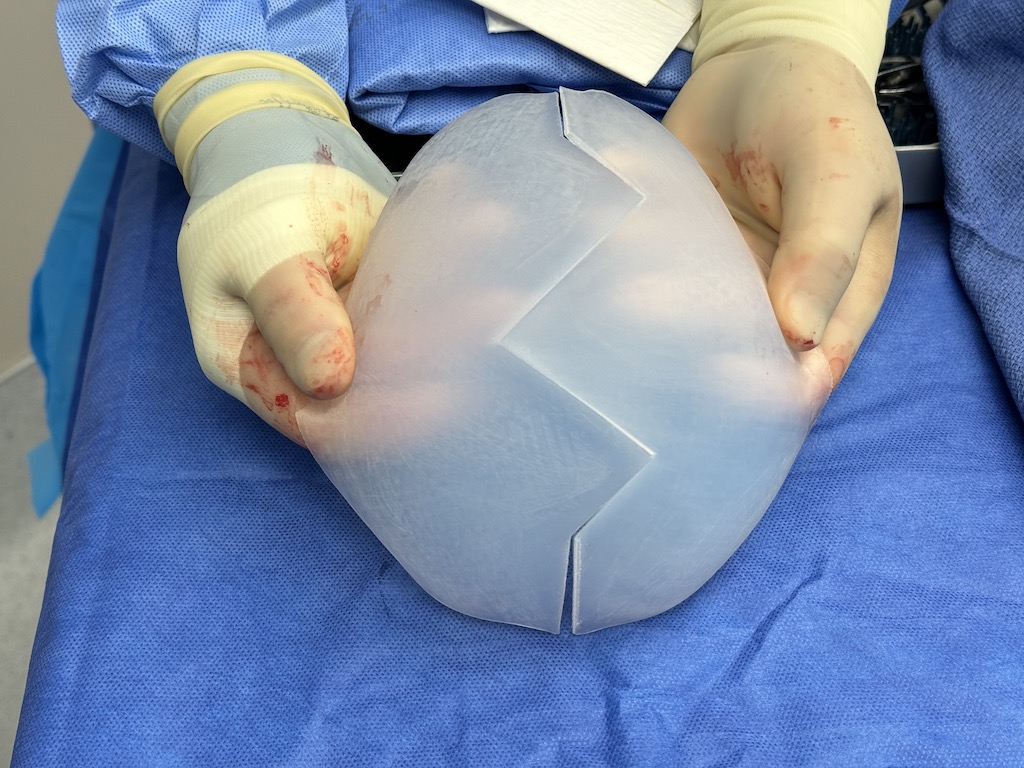

Desire for large overall skull augmentation procedure. Two piece custom skull implant designed with 250ccs volume.

1st stage scalp expander placed and inflated to 225ccs. 2nd stage two piece skull implant placed 4 months later.

Desire for large overall skull augmentation procedure. Two piece custom skull implant designed with 250ccs volume.

1st stage scalp expander placed and inflated to 225ccs. 2nd stage two piece skull implant placed 4 months later.